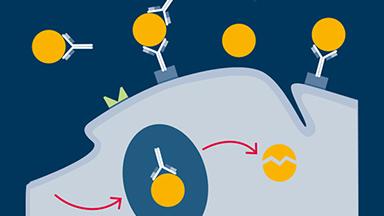

This ITI Academy Learning Module will review basic concepts of pharmacology: the study of how these chemicals affect the body and how they potentially interact with other substances that may have been co-administered.

Many of the patients that enter a dental office seeking treatment will have conditions requiring one or more forms of medication. Most older patients will be taking regular medications to manage chronic illnesses.

Some may present using one or more types of chemical assistance. All of these substances have the potential to interact with medications that you may prescribe and/or administer.

They, or the diseases that they are being used to treat or manage, may have direct or indirect impacts on dental treatment.